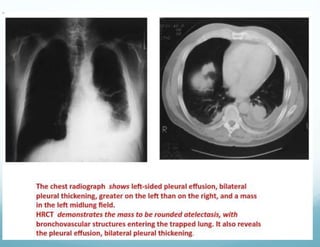

ROUNDED ATELECTASIS

 Caused by scarring of the visceral and parietal pleura

and the adjacent lung, with the pleural reaction folding

over on itself.

 The pleural surfaces then fuse to one another,

trapping the underlying lung and leading to

atelectasis.

 As a result of this alteration, a mass lesion that mimics

Lung cancer can be seen on PA chest Radiograph

 This lesion is most easily appreciated to be a

PSEUDOTUMOR with the use of CT scanning

 HRCT can non invasively demonstrate continuity to

areas of diffuse pleural thickening, evidence of volume

loss in the adjacent lung, or a characteristic comet tail

of vessels and bronchi sweeping into wedge shaped

mass.

 HRCT scans localised most cases of rounded

atelectasis to the lower, posterior portion of lung(right)